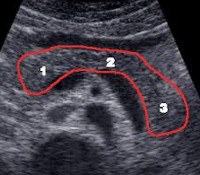

Ultrasound of the pancreas to a child.

Во время УЗИ поджелудочной железы ребенок лежит на спине, вправо и влево. Основными ориентирами для определения топографии железы являются сосудистые структуры (брыжеечная, селезенка и верхние портальные вены, аорта, верхняя брыжеечная артерия) и позвоночник. Сканирование поджелудочной железы проводится в продольной и поперечной плоскостях с поддержанием дыхания. Использование разных проекций и углов наклона датчика позволяет получить наилучшую визуализацию всей поджелудочной железы.

Ультразвуковое исследование поджелудочной железы дает ребенку ценную информацию о форме, контурах и структуре органа. размер головы, тела и хвоста железы; Диаметр проводки канала. У детей эхогенность поджелудочной железы схожа с печенью, паренхима однородная, контуры четкие и ровные, переднезадние размеры соответствуют показателям возраста и роста, основное течение поджелудочной железы не расширено.

При различных типах патологических процессов в поджелудочной железе могут быть обнаружены изменения в эхоструктуре паренхимы, контурах и размерах железы, протяженности протока поджелудочной железы, деформации верхней брыжеечной и нижней полой вены.